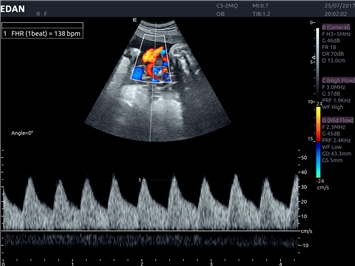

• Акушерства и гинекологии

Импульсно-волновой допплер:

Да

Триплексное сканирование: